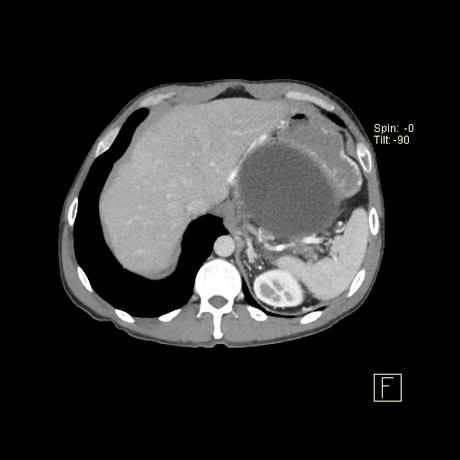

producen por la alteración de la estructura del conducto pancreático con la consiguiente pérdida y acumulación de jugo pancreático que da lugar a una necrosis grasa hemorrágica. No están revestidos por epitelio (por lo tanto, “pseudoquistes”), sino que una reacción inflamatoria grave da como resultado la encapsulación del quiste por tejido de granulación fibrosado. Esto suele tardar de 4 a 6 semanas 8,9 . En aproximadamente el 50% de los casos, el quiste conserva una comunicación con el conducto pancreático 2 . Estos quistes son más problemáticos de tratar y es más probable que reaparezcan.